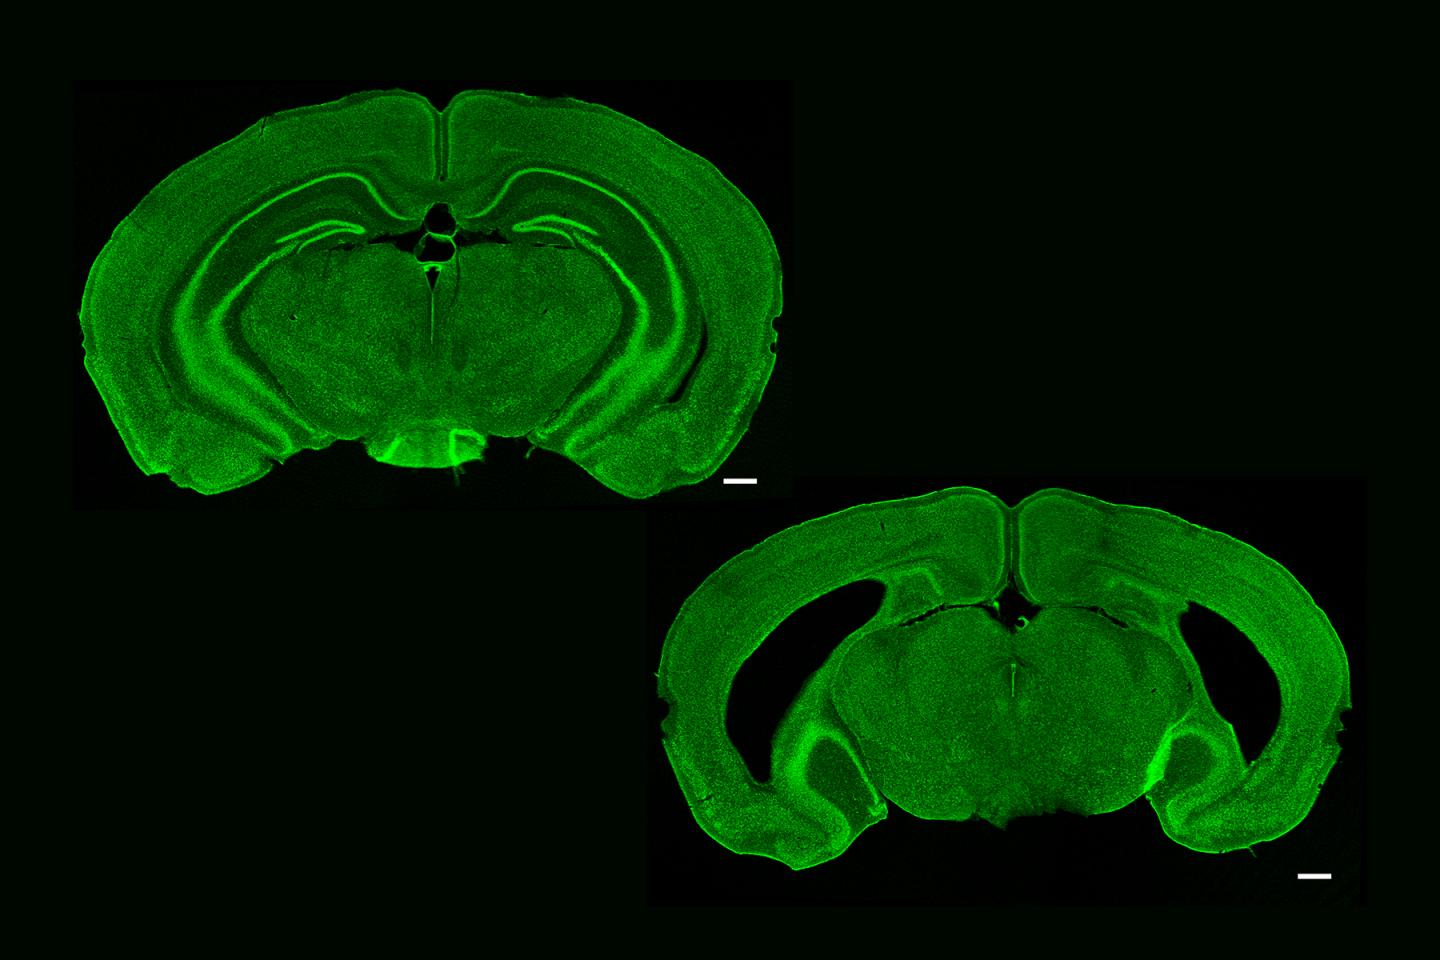

But the researchers were curious about whether and how the hippocampus might contribute to these forms of memory and cortical plasticity. After all, like some other forms of memory that depend on the hippocampus, SRP only takes hold after a period of "consolidation," for instance overnight during sleep. To test whether there is a role for hippocampus, they chemically removed large portions of the structure in a group of mice and looked for differences between groups in the tell-tale electrical response each kind of recognition memory should evoke.

Mice with or without a hippocampus performed equally well in learning SRP (not only measured electrophysiologically but also behaviorally), suggesting that the hippocampus was not needed for that form of memory. It appears to arise, and even consolidate, entirely within the visual cortex.

Visual sequence plasticity, however, did not occur without an intact hippocampus, the researchers found. Mice without the structure showed no elevated electrical response to the sequences when tested, no ability to recognize them in reverse or when delayed and no inclination to "fill in the blank" when one was missing. It was as if the visual sequence --and even each image in the sequence--was not familiar.